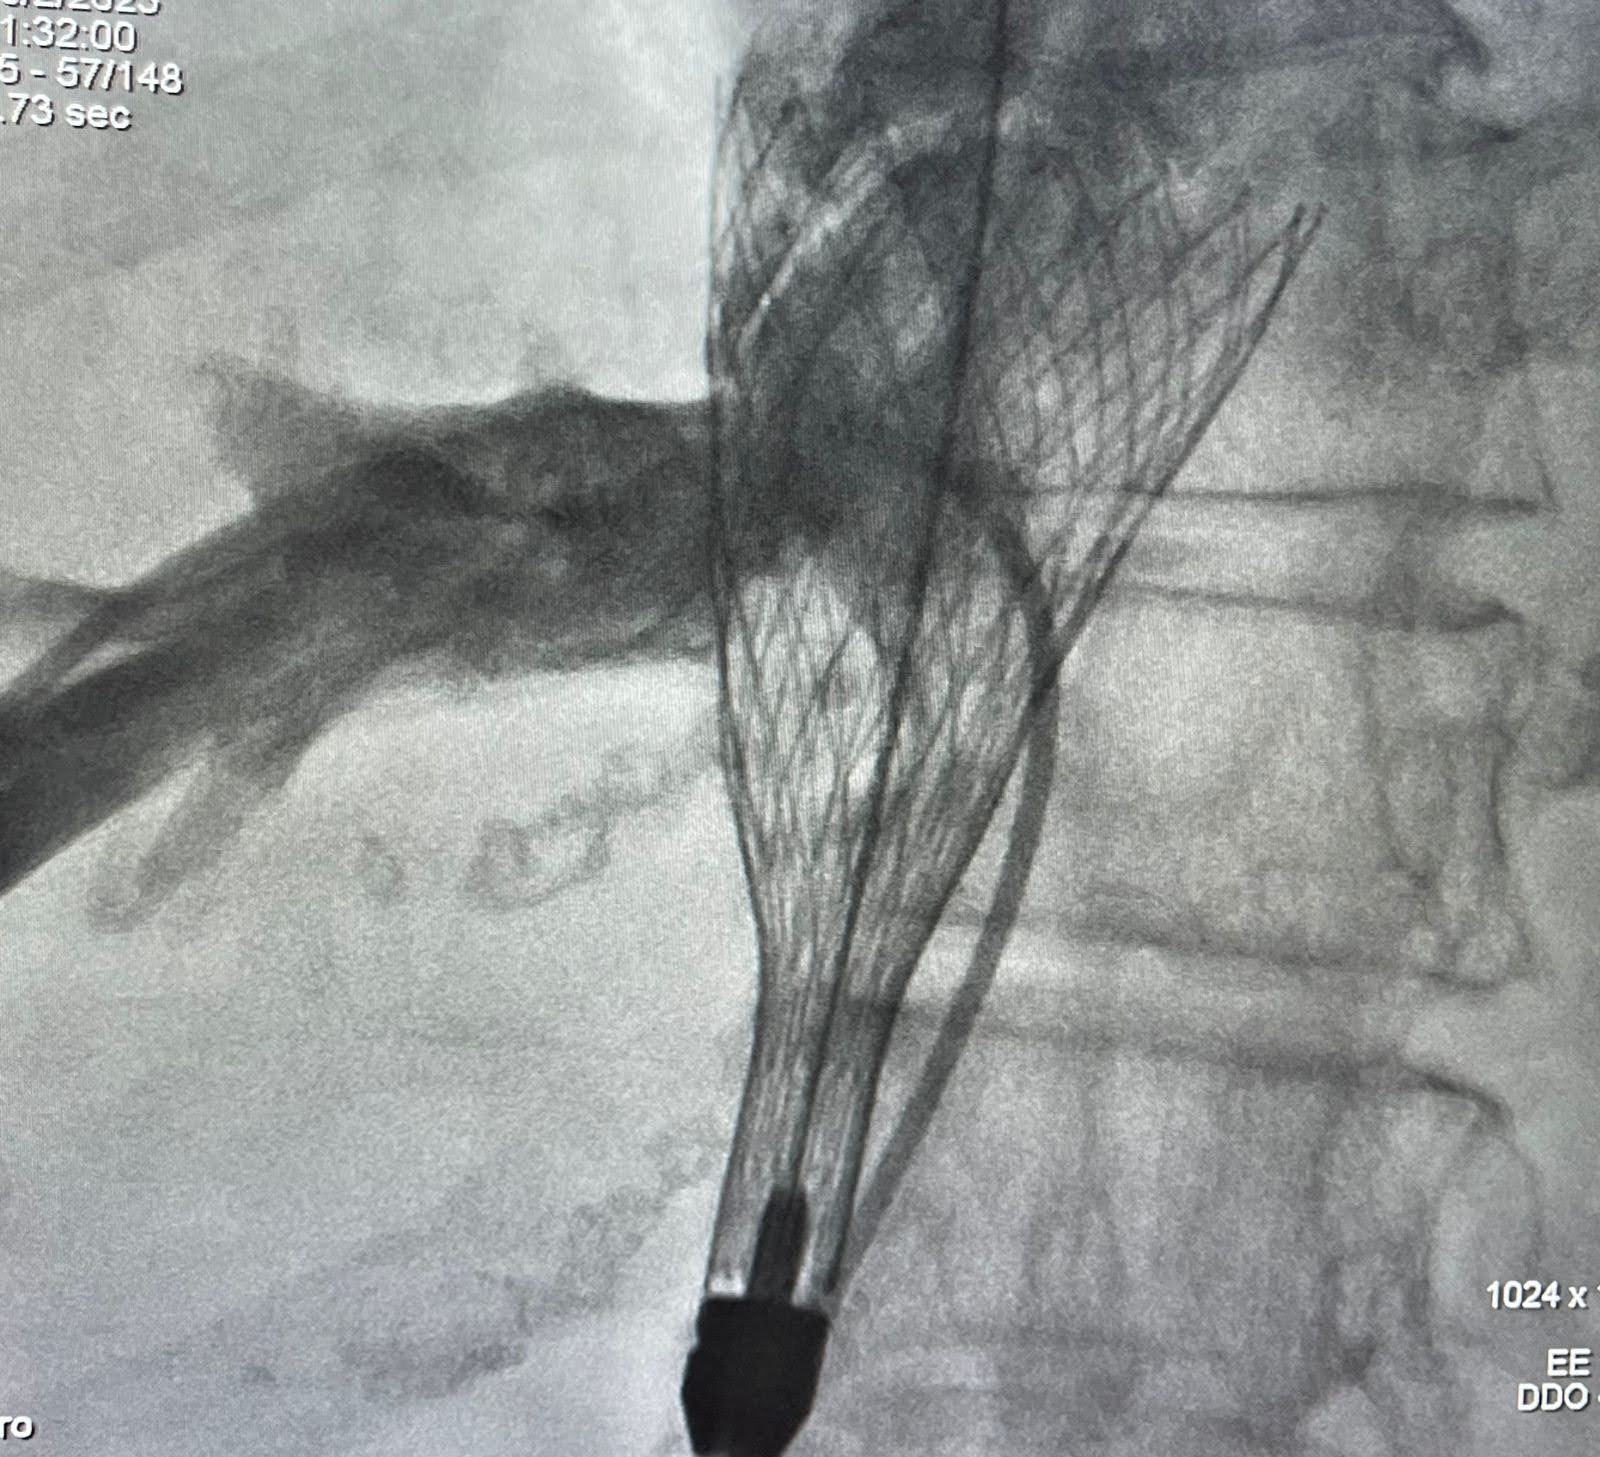

A terapia com auxílio de cateteres dispensa a necessidade de abrir o peito do paciente, sendo menos invasiva e proporcionando uma recuperação mais rápida. Dr. Guedes esclarece que a terapia transcateter da válvula tricúspide, através do sistema TricValve, consiste no implante de próteses valvadas na veia cava superior e veia cava inferior através de um cateter colocado pela veia profunda do paciente. O procedimento foi realizado sob sedação leve e anestesia local, sem necessidade de intubação e ventilação mecânica.

*Foto: Divulgação